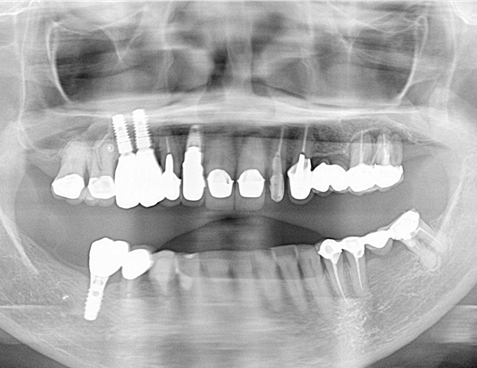

レントゲン写真でも理想的な位置

に埋入できました。